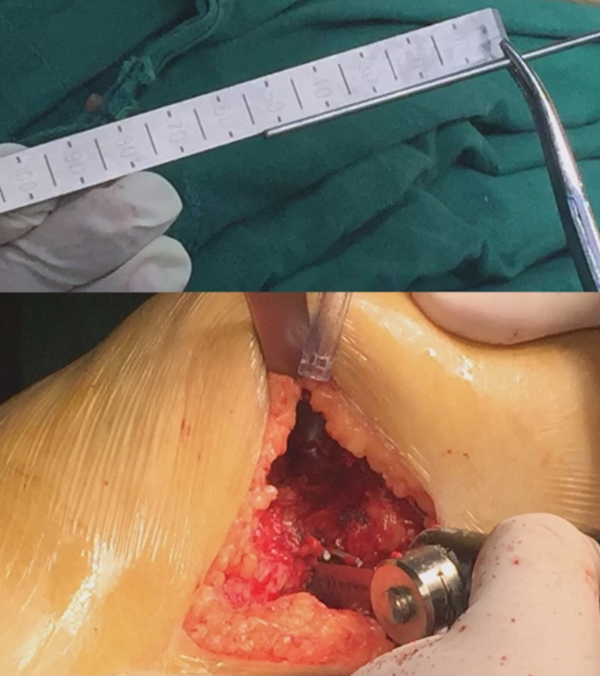

术前推荐用力线杆核实力线,通常在术前计划时,需要做下肢全长片,但是有些医院的下肢全长片为拼接而来,可能会存在拼接误差,继而影响术前计划的准确性,因此推荐术前再次使用力线杆评估力线,以保证与术前计划一致。

合页点和截骨线已确定好,按照术前计划打入导针,测量截骨深度。